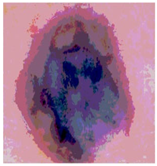

| Segmented Image | R | G | B |

|---|---|---|---|

![]() | ![]() | ![]() | ![]() |